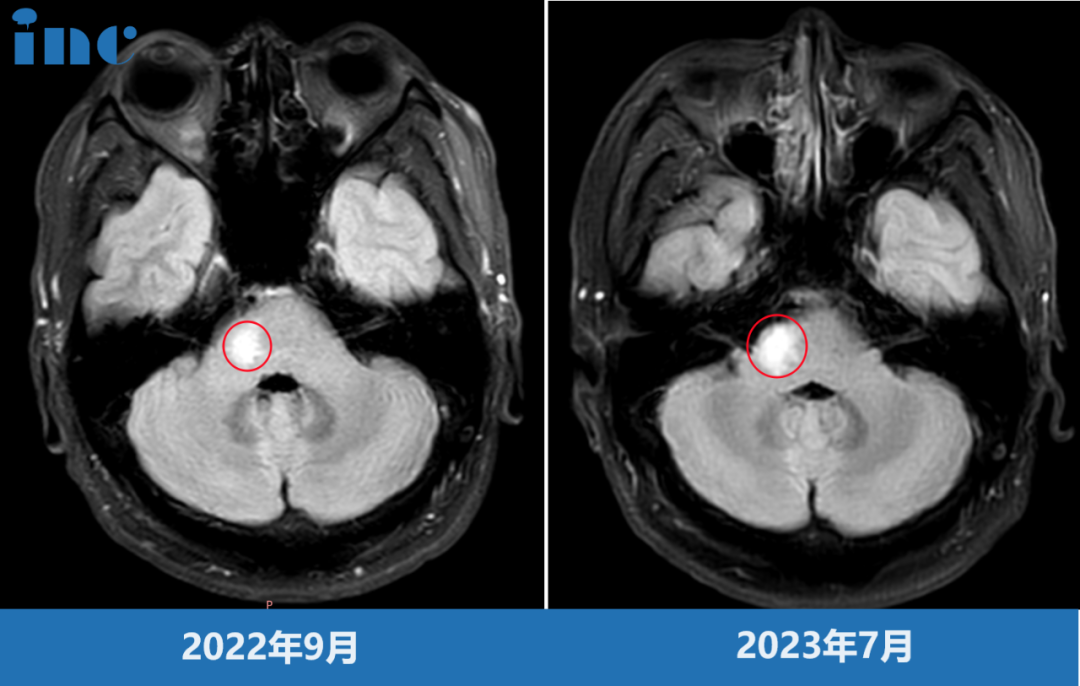

脑干-桥臂胶质瘤长大,三根重要神经包绕肿瘤

命运总会在人意气风发的时候,悄悄伸出脚把你绊倒。韩先生、30出头、高级工程师,正是家庭和事业蒸蒸日上的时候,这时却被胶质瘤病魔的触角缠住。短短不到一年,由初次诊断的疑似脱髓鞘病变,到病灶增大、怀疑胶质瘤。一边需要全身心投入高工作之中,一边四处求医。“桥臂位置处于大脑深部,手术难度、风险都很大,不建议手术。”原本充满朝气的生活如今度日如年,心力憔悴的韩先生此时无路可走。

韩先生术前影像

脑干桥臂位置,肿瘤还被面神经,滑车神经,听神经等重要神经包绕,手术难度之大不言而喻。巴教授是他们然后的希望。2023年9月29日,中秋节当天,巴教授为韩先生成功手术。